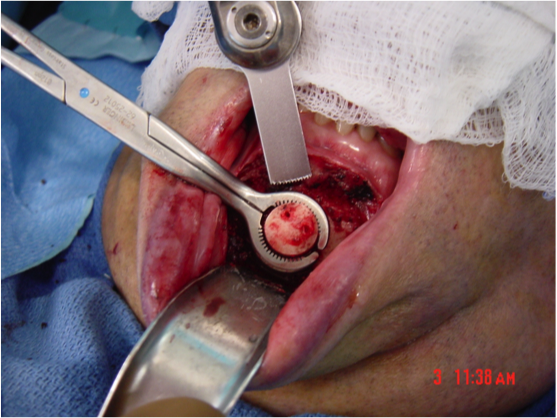

This procedure places tension on the tongue, limiting the posterior from shifting during sleep. The procedure starts with a small incision made inside the lower lip. Then, the surgeon moves away all the soft tissue to expose the lower jaw. Small rectangular cuts are then made in the lower jaw directly in front of the lower front teeth. This area attached to the genioglossus muscle is then moved forward and turned slightly. To hold this bone fragment in place, the surgeon puts in a titanium screw to immobilize it.

The photos on this website are from real surgeries performed by Dr. Ulloa. Due to the

graphic nature of the images and content, viewer discretion is advised.